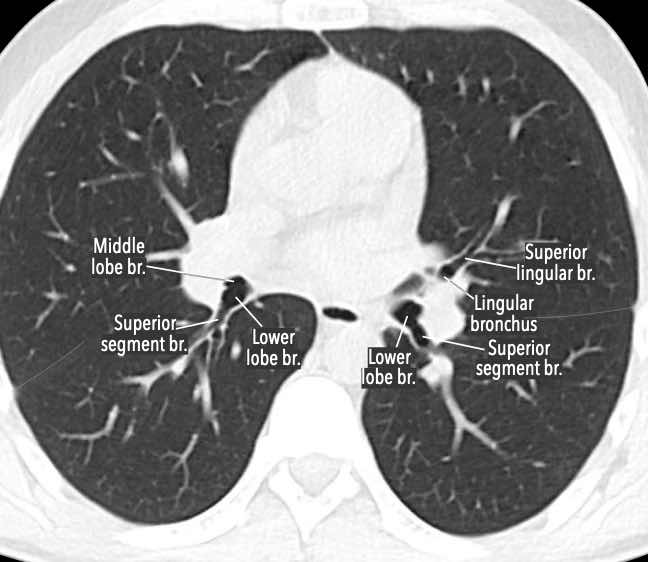

Phế quản trên CT

Cuộn qua các hình ảnh để quan sát khí quản phân chia thành phế quản chính phải và trái, sau đó tiếp tục phân chia thành các phế quản thùy và phế quản phân thùy.